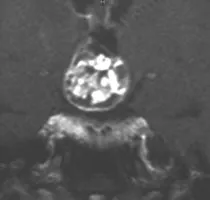

在寻找施罗德教授后,该患者向他叙述了自己的病史。他出现的主要症状包括疲劳、性能下降和勃起功能障碍,双颞侧偏盲。对于颅咽管瘤,磁共振成像(MRI)是首选的检查方法。该患者的MRI显示鞍上颅咽管瘤,肿瘤侵入第三脑室。内分泌检查显示垂体功能部分不足。

使用对比剂的T1加权矢状和冠状MRI图像显示鞍上和室内的颅咽管瘤(双颞侧偏盲)